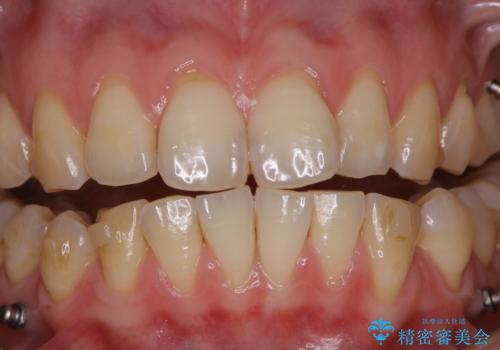

インビザライン矯正治療中のPMTC

インビザラインでの治療中の患者様のクリーニング前後写真です。

- インビザライン矯正中に茶色が気になるとのことで来院されました。PMTC30分コースを行いました。